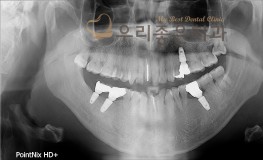

우리좋은치과 치아 상실 및 골소실 → 뼈이식 및 임플란트 보철 치료(김**2017...

No.295

임플란트

2019-05-31

1538